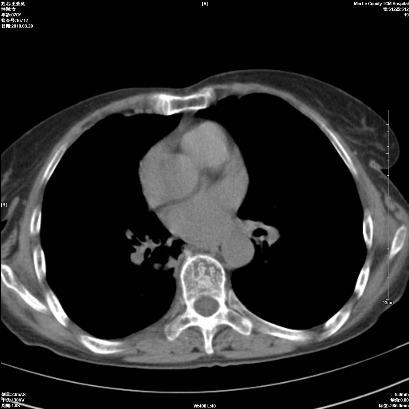

标题: CT25424:女性,70岁,胸闷、咳嗽月余。 [打印本页]

右肺上叶支气管开口阻塞,上叶呈不均匀致密影,右肺中下叶内见斑片状密度增高影,上叶见钙化点,纵隔内见钙化淋巴结,桶状胸,右下肺动脉增粗,残根征,意见:1.右肺中心性肺癌;2.右肺陈旧性结核;3.肺心病。

1)考虑右肺中央型肺癌伴右肺上叶肺不张,右肺门淋巴结转移;建议行支纤维镜检查。2)右肺中叶、下叶及左肺上叶舌段感染性病变。3)肝内多发低密度影,不排除转移瘤可能;建议行ct增强扫描检查。

ct所见:右肺上叶肺不张,呈软组织密度影向肺门区聚拢,其内可见含气段支气管及细支气管影,病灶内尚可见钙化结节。右肺上叶支气管狭窄,段支气管壁可见钙化。右肺下叶背段、右肺中叶见不规则小片絮状影及纤维条索影,形态较僵硬。右肺中叶胸膜旁可见多个小结节影。纵膈内见钙化淋巴结。

分析:右侧胸廓及右肺体积缩小,说明病变时间比较长了,应该是有数年的时间了,如果是短期内出现的肺不张,只会引起纵膈向患侧移位,而不会引起胸廓的塌陷。不张的肺组织内可见含气支气管影,说明右肺上叶支气管没有完全中断,只是狭窄。右肺中叶、下叶散在不规则病灶,部分呈纤维化改变。纵膈内的淋巴结大部分钙化。因此,本例给我的感觉良性病变的可能是大。

结论:考虑右肺上叶支气管内膜结核合并右肺上叶肺不张;右肺中叶、下叶陈旧性肺结核改变。